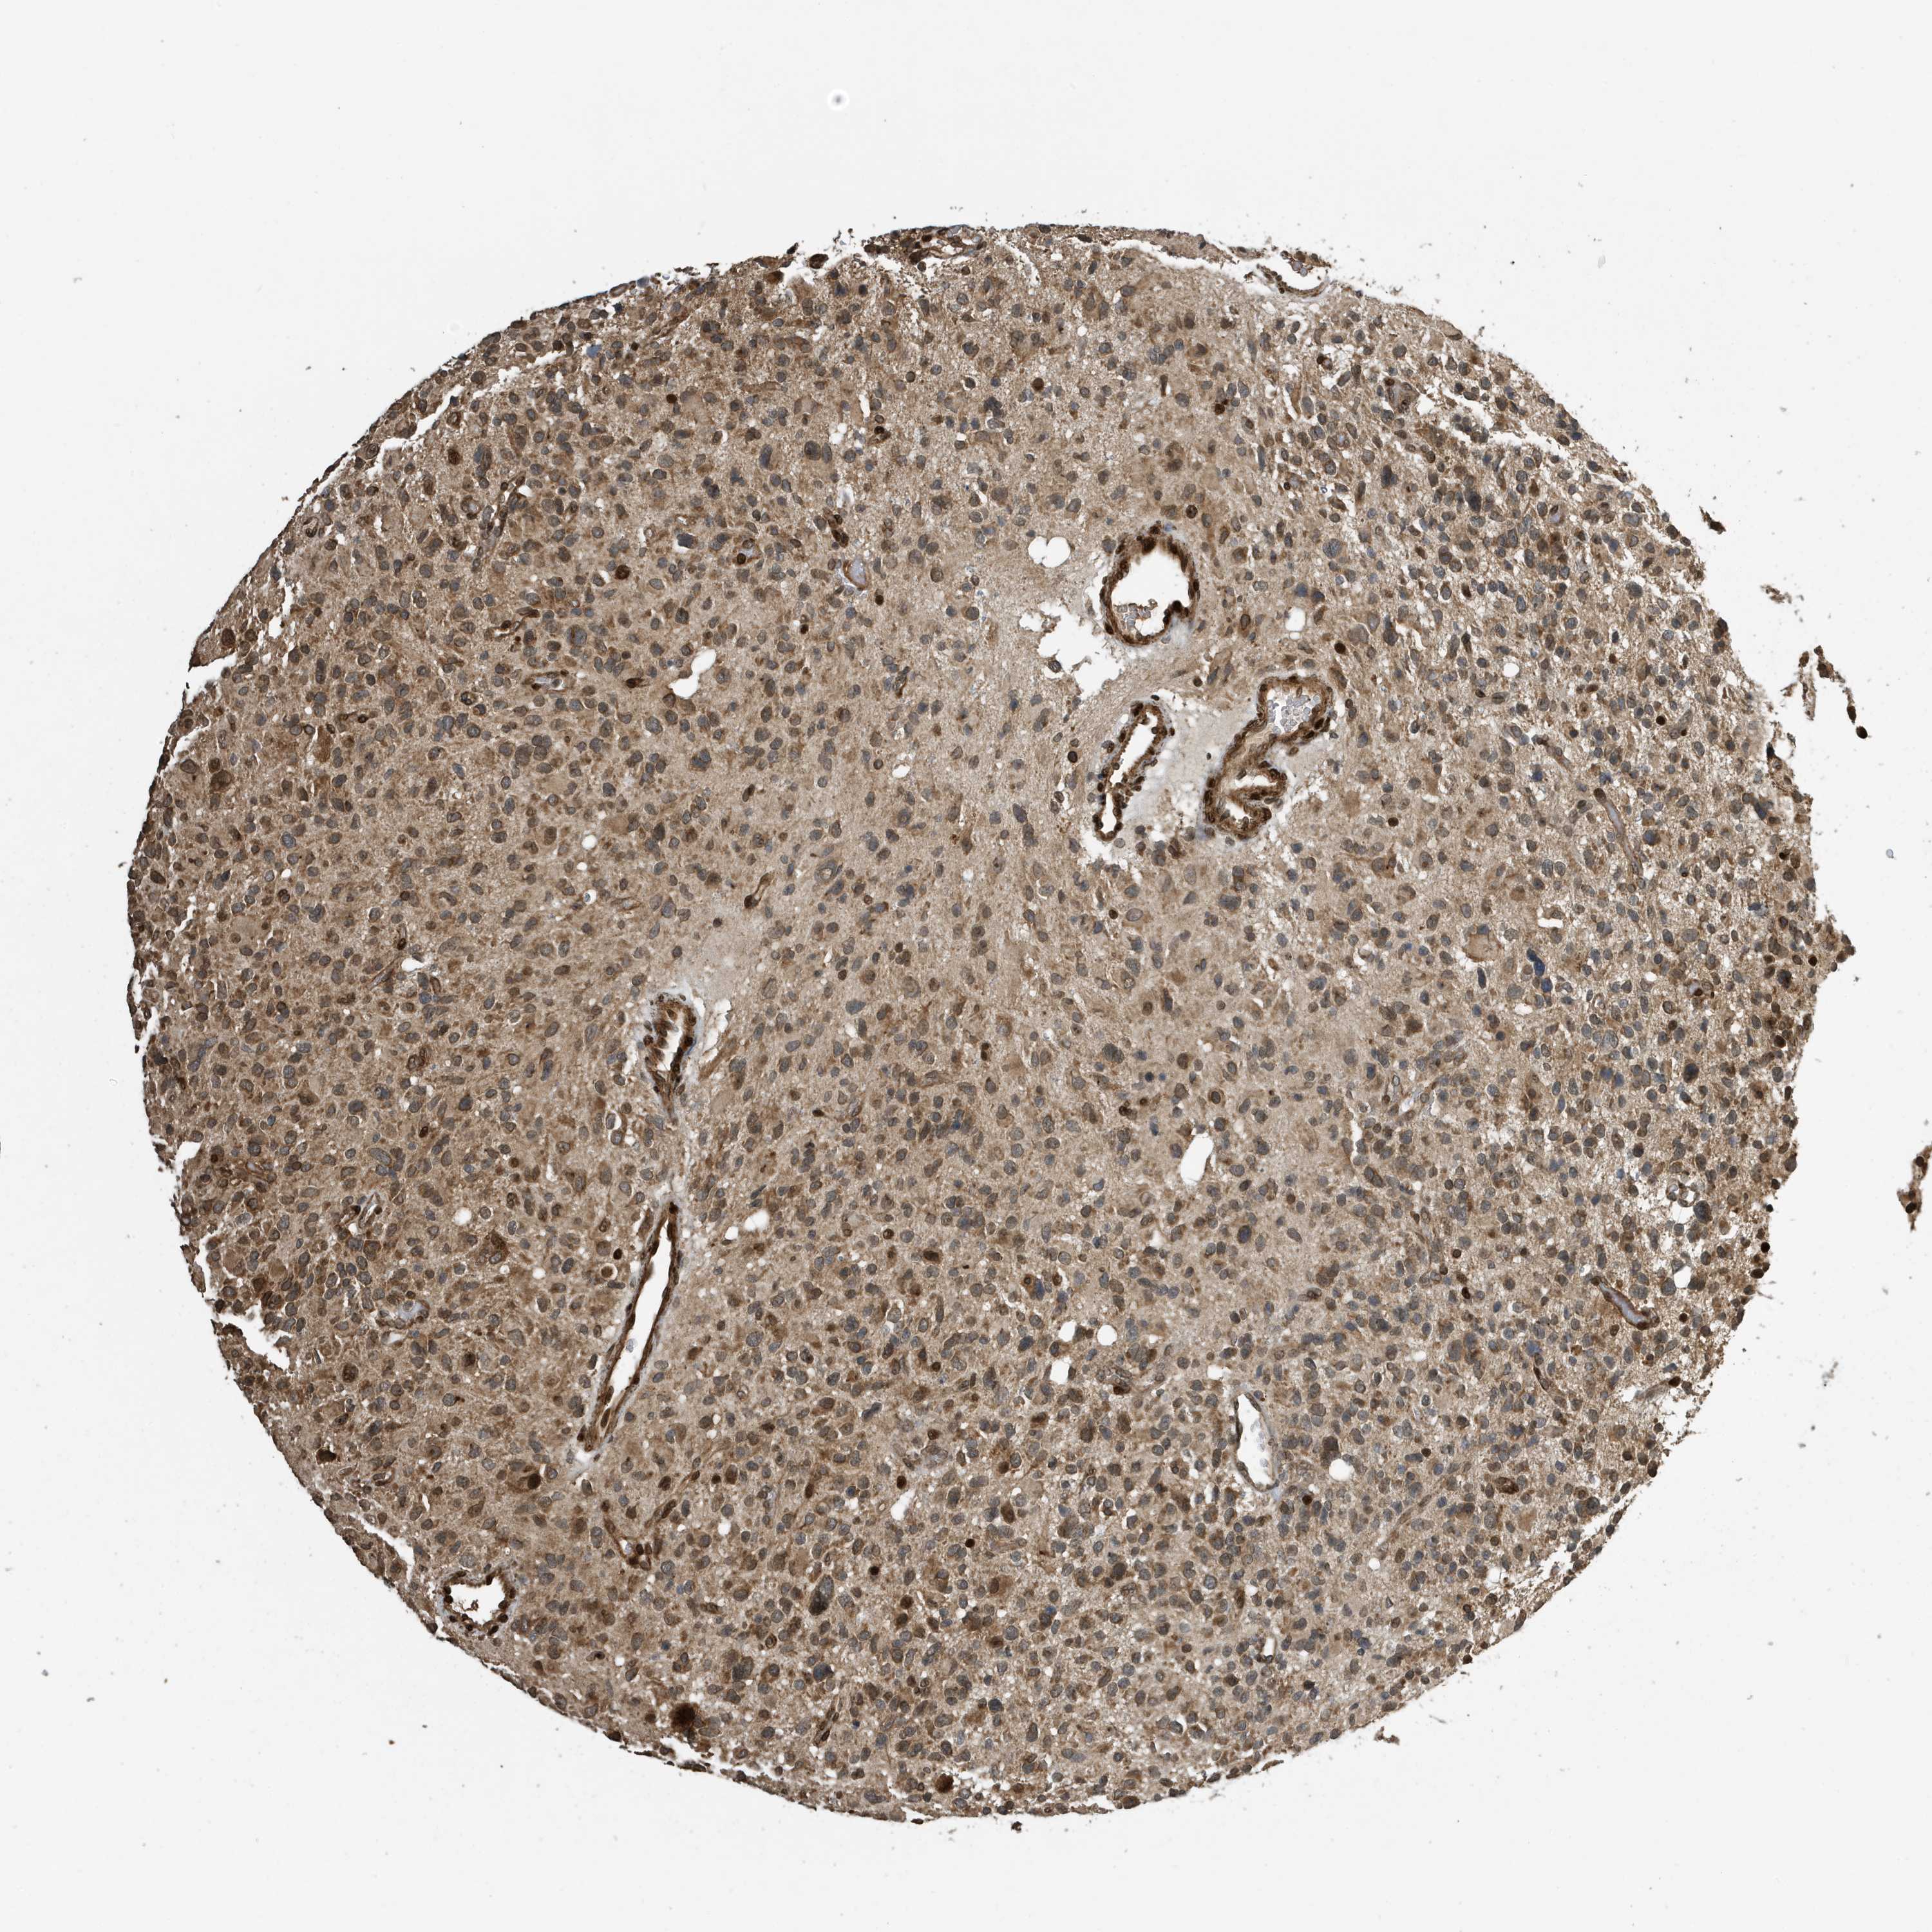

GLIOMA - Protein expressioni

A mouse-over function shows sample information and annotation data. Click on an image to view it in a full screen mode. Samples can be filtered based on level of antibody staining by selecting one or several of the following categories: high, medium, low and not detected. The assay and annotation is described here.

Note that samples used for immunohistochemistry by the Human Protein Atlas do not correspond to samples in the TCGA dataset.

Antibody stainingi

Antibody staining in the annotated cell types in the current human tissue is reported as not detected, low, medium, or high, based on conventional immunohistochemistry profiling in selected tissues. This score is based on the combination of the staining intensity and fraction of stained cells.

Each image is clickable and will lead to virtual microscopy that enables deeper exploration of all samples and also displays staining intensity scores, fraction scores and subcellular localization as well as patient and tissue information for each sample.

Antibody CAB034070

Staining

High

Medium

Low

Not detected

Intensity

Strong

Moderate

Weak

Negative

Quantity

>75%

75%-25%

<25%

None

Location

Nuclear

Cytoplasmic/membranous

Cytoplasmic/membranous,nuclear

Glioma, malignant, High grade

Glioma, malignant, Low grade